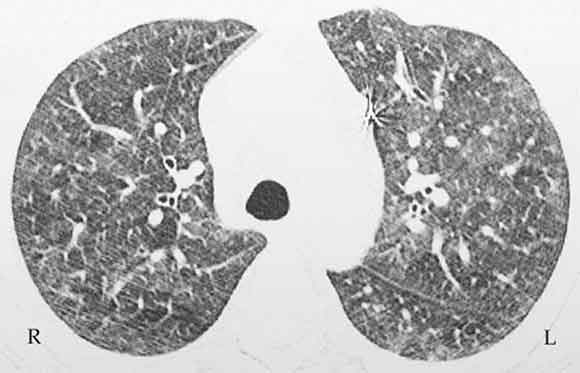

A chest x-ray demonstrated bilateral ground glass infiltrates, predominantly in the basal zones. High-resolution computed tomography (CT) of the chest revealed bilateral patchy ground glass opacities (Box 1). Spirometry showed a forced vital capacity (FVC) of 65% predicted, a forced expiratory volume (FEV1) of 68% predicted, and FEV1/FVC of 104%. An echocardiogram was normal. A nerve conduction velocity study showed axonal involvement, with reduced nerve conduction velocity in the right radial and left superficial peroneal nerves. CT of the paranasal sinuses showed chronic pansinusitis. Histopathological examination of the open-lung biopsy showed leukocytoclastic vasculitis, granuloma formation, and extravascular eosinophilic infiltration (Box 2). Renal biopsy showed pauci-immune, crescentic glomerulonephritis. Renal vessel Doppler ultrasonography and renal angiography gave normal results and ruled out any renal vessel involvement. The patient tested positive for perinuclear antineutrophilic cytoplasmic antibodies (ANCAs) and negative for cytoplasmic ANCAs by the indirect immunofluorescence method. A more specific enzyme-linked immunosorbent assay (ELISA) for anti-myeloperoxidase was positive, and another, for anti-proteinase 3, was negative. These tests ruled out Wegner’s granulomatosis. Antinuclear factor, anticardiolipin antibodies, hepatitis B surface antigen, and serological tests for hepatitis C and HIV were negative, thus ruling out significant secondary causes of vasculitis.

The patient was treated with prednisolone (1 mg/kg per day, orally) and her condition showed marked clinical as well as radiological improvement. She became afebrile after 4 days, normotensive after 4 weeks, and her palpable purpura disappeared after 6 weeks. High-resolution CT of the chest, repeated at 4 and 8 weeks, showed progressive resolution of ground glass infiltrates. Repeat urinalysis showed resolution of proteinuria and haematuria at 8 weeks. The prednisolone dose was tapered over 8 weeks to a maintenance dose of 0.125 mg/kg every second day. Additional management included surgical amputation of all left-hand fingertips and physiotherapy for the motor weakness.